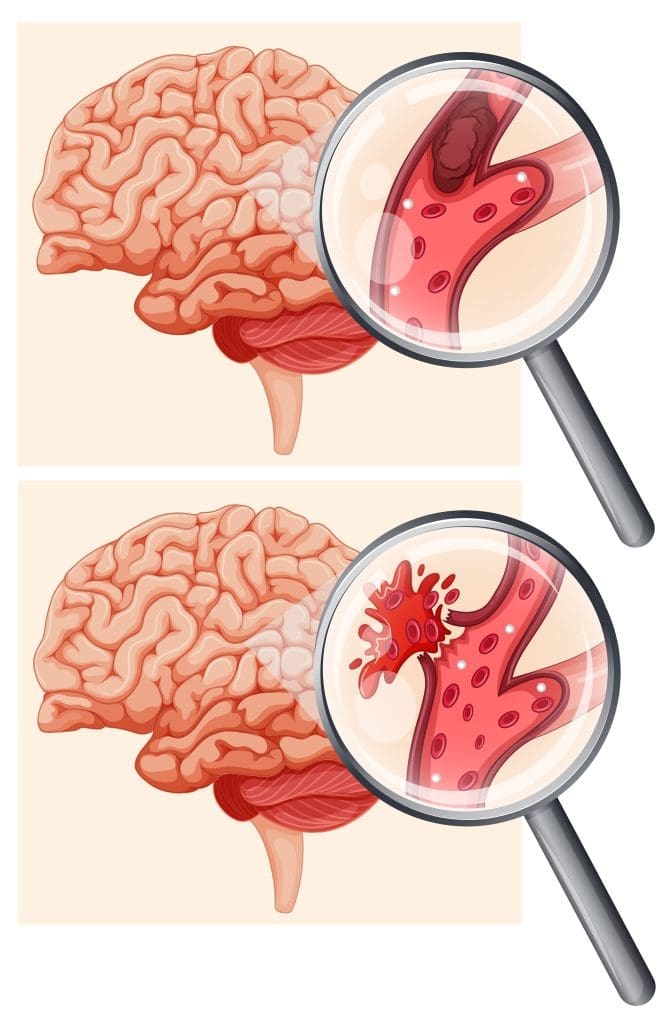

يتم وصف أورام الدماغ الدموية كتجمعات للدم في تجويف الجمجمة. وتحدث هذه الحالة بسبب تمزق الأوعية الدموية داخل القحف، نتيجة لارتطام الرأس، وهذا هو السبب الأكثر شيوعًا. وقد يؤدي ذلك في بعض الأحيان إلى ضغط على أنسجة المخ.

قد تكون الحالة أيضًا نتيجة لاصطدام الرأس بشكل بسيط يتلاشى بمفرده، أو بسبب بعض العلاجات الدوائية. في حالات أخرى قد يكون الاحتشاء الدماغي غير محدود، وسيتعين في تلك الحالة إجراء جراحة لإزالة الأورام الدماغية.

يحدث الورم الدموي فوق الجافية أو خارجها في المنطقة الموجودة بين الجمجمة وطبقات الأم الجافية، في حالة تدمير أو تمزق أحد الشرايين، وبالتالي يتدفق الدم مسبباً الورم، مما يؤدي للضغط على الأنسجة الدماغية. هذا النوع هو الأكثر إنتشاراً بين أنواع أورام الدماغ الدموية، وفي حالات شديدة قد يؤدي ذلك إلى الوفاة إذا لم يتم اللجوء للجراحة.

يقوم الأطباء بتصنيف الأورام الدموية التي تحدث تحت الجافية وفقًا لسرعة تطورها، وكمية النزيف الذي يحدث، ومدى الضرر الناتج عن النزيف. هناك أنواع مختلفة من الأورام الدموية تحت الجافية.